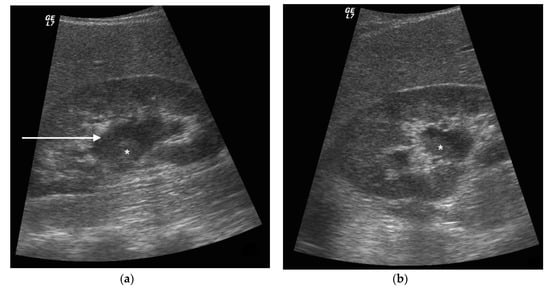

3. Ultrasound